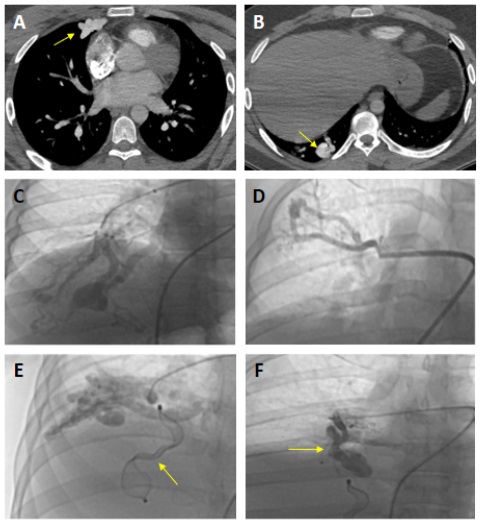

A 27-year-old man presented to the emergency department with complaints of syncope, dyspnea, and fatigue. Physical examination revealed left-sided mild hemiparesis, platypnea, and continuous murmur on right middle lobe lung auscultation. Pulse oximetry analysis revealed worsening hypoxemia during the upright position (78%) and ameliorating hypoxemia during the supine position (84%). Thoracic computed tomographic angiography (CTA) demonstrated multiple pulmonary arteriovenous malformations (PAVM) (Figure A,B). We suspected hereditary hemorrhagic telangiectasia. However, the patient did not meet the other diagnostic criteria except for PAVMs. Pulmonary angiography was performed to demonstrate the PAVMs in detail, and it was determined that the right-sided malformations were enormous, while the left-sided malformations were relatively small (Figure C, D, E, F, Video ).

The heart team decided to occlude the right-sided PAVMs by percutaneous approach. Since there was no vascular plug in our laboratory, we decided and occluded the malformations with the atrial septal defect (ASD) closure devices (Figure E, F). At a 5-month follow-up, the patient’s capillary oxygen saturation reached 94% in the supine position and 91% in an upright position, and the symptoms were completely relieved.